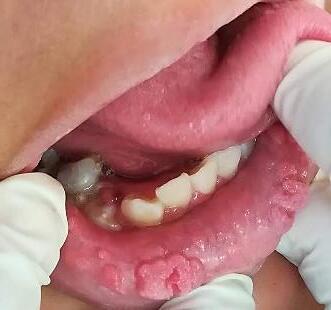

Presentación de caso clínico

Paciente masculino de 63 años de edad, presenta lesión en reborde alveolar

zona de segundo y tercer molar inferior, eritematosa, de forma irregular, de bordes elevados, consistencia blanda que se desprende fácilmente, causa dolor persistente a la manipulación con presencia de sangrado a la palpación y exudado. (Fig.10) de 2 meses de evolución, ha sido tratado con agua oxigenada y tratamientos caseros sin mejoría, con antecedentes de tabaquismo y alcohol. A la exploración radiográfica se aprecia lesión radiolúcida maldelimitada(Fig.11).

Nota:Úlceraquenocicatriza(FotocortesíaDra.JazmínFuentesMarroquín).

Fig 10.

Úlcera que no cicatriza

Fig. 11

Ortopantomografía; lesión radiolúcida mal delimitada localizada en tercer cuadrante, autoría propia.

Nota:FotocortesíaDra.JazmínFuentesMarroquín

Se tomó biopsia incisional donde se observóepitelioescamosoestratificadoque se continua con masas células neoplásica conpleomorfismocelularynuclear,pérdida de la relación núcleo citoplasma, mitosis aberrantes y aumentadas, nucleolos evidentes y queratinización individual y grupal que infiltraban tejido conjuntivo subyacente; (Fig. 12) por lo que se diagnósticacomoCarcinomaoraldecélulas escamosas, Se realizo PCR al bloque de parafinapor indicación deloncólogodonde fuepositivoalVPH52,porloqueseindicó inmunoterapianeoadyuvante